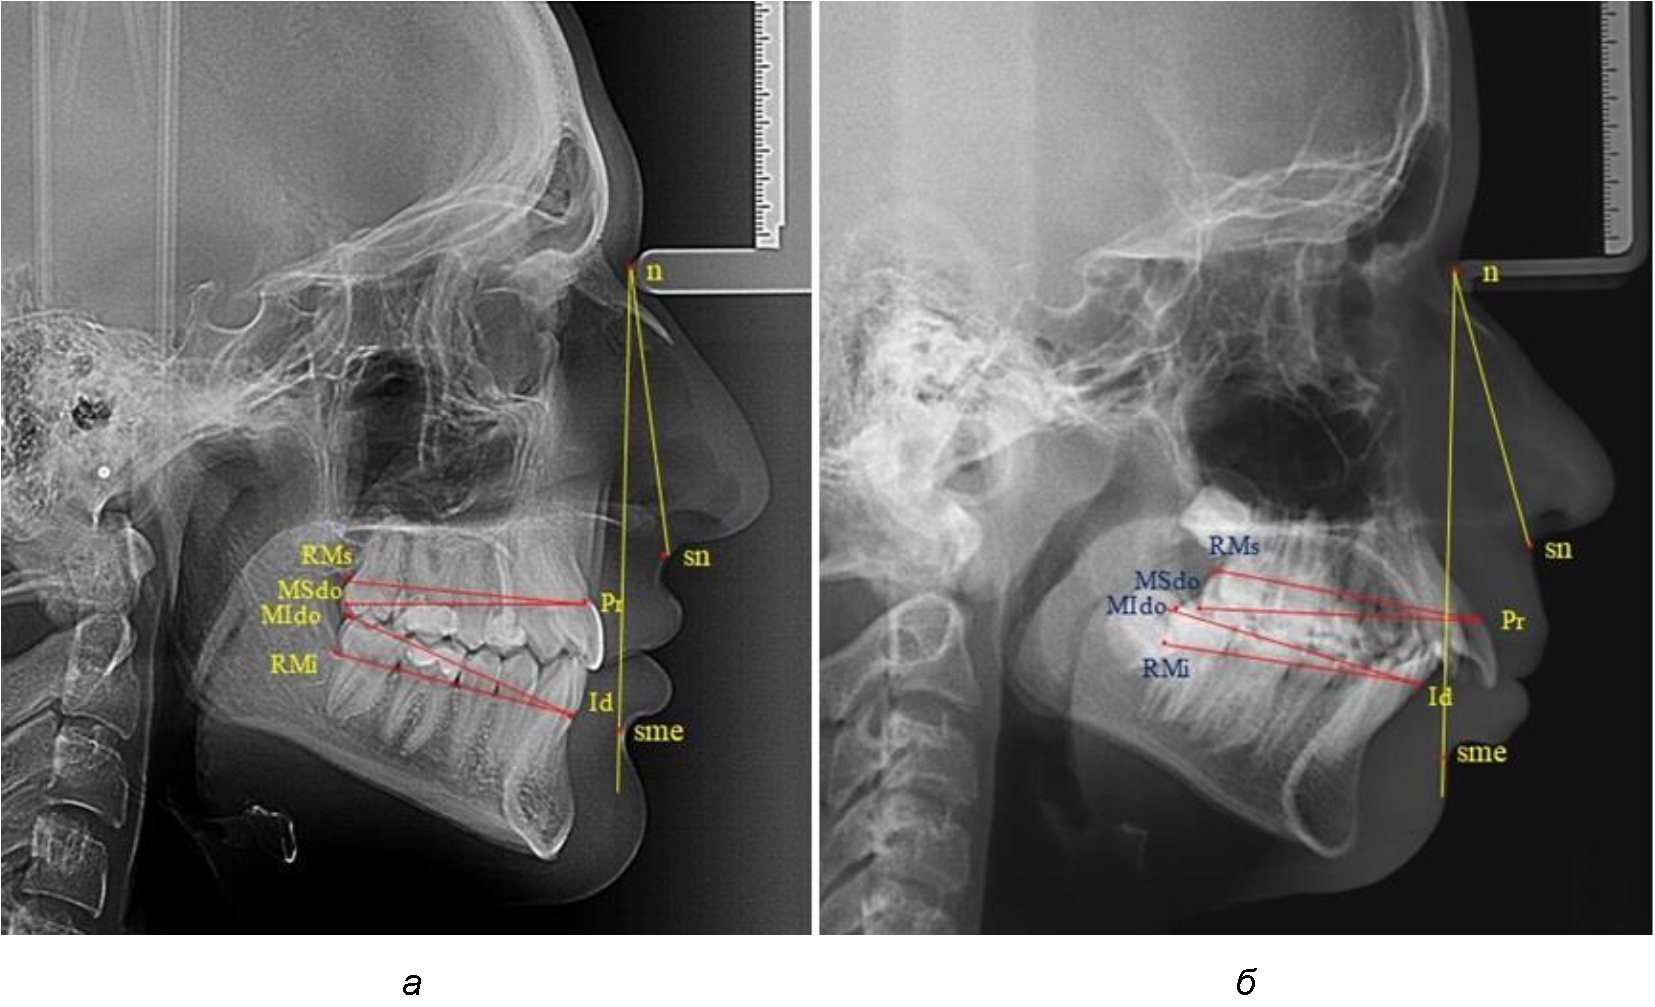

Измеряли межальвеолярное расстояние на верхней челюсти (Pr-RMs) и на нижней челюсти (Id-RMs) и сравнивали показатели между собой. Альвеолярно-окклюзионный размер на верхней челюсти (Pr-MSdo) сравнивали с аналогичным параметром нижней челюсти (Id-MIdo). При анализе 32 телерентгенограмм с дистальной окклюзией использовали те же ориентиры (рис. 1).

Рис. 1. Точки и линии телерентгенграмм при физиологической (а) и дистальной (б) окклюзии

При физиологических вариантах прикуса дистальные окклюзионные точки моляров, как правило, располагались практически рядом, в то время как при дистальном соотношении нижние моляры анализируемый окклюзионные точки, как правило, располагались позади верхних.